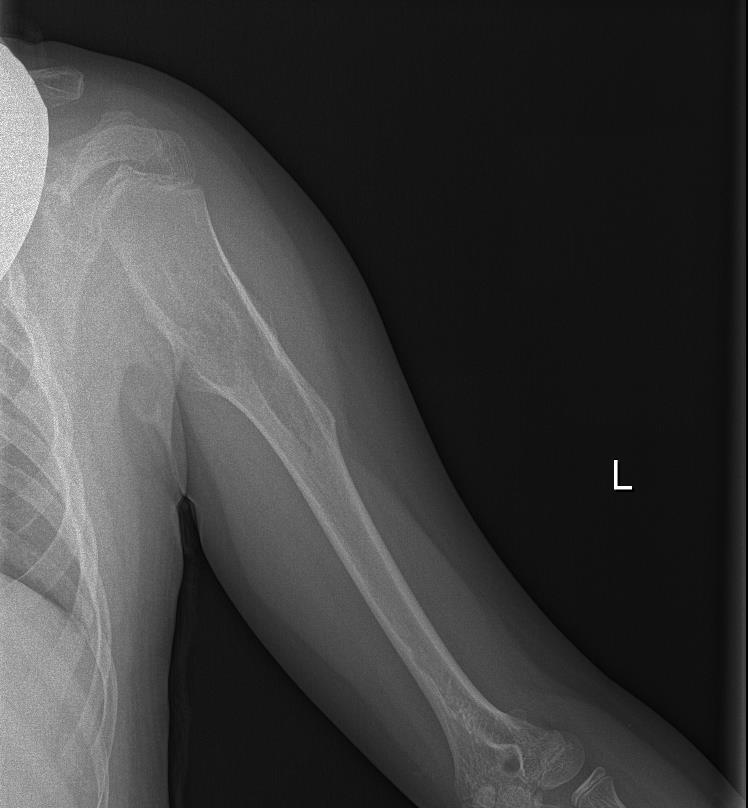

Radiografía de Miembro superior izquierdo: Se visualiza lesión lítica metafiso-diafisaria en húmero izquierdo expansiva con excrecencias óseas y margen estrecho con hueso sano.

Juicio clínico: Exostosis múltiple chereditaria. Osteocondromas múltiples (ORPHA 321) de novo.

Diagnóstico diferencial: Osteocondroma plano vs Displasia fibrosa.